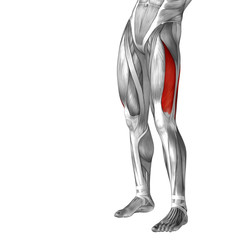

Podobny obraz Medical Elbow Anterior View X-Ray Radiograph Illustrating...